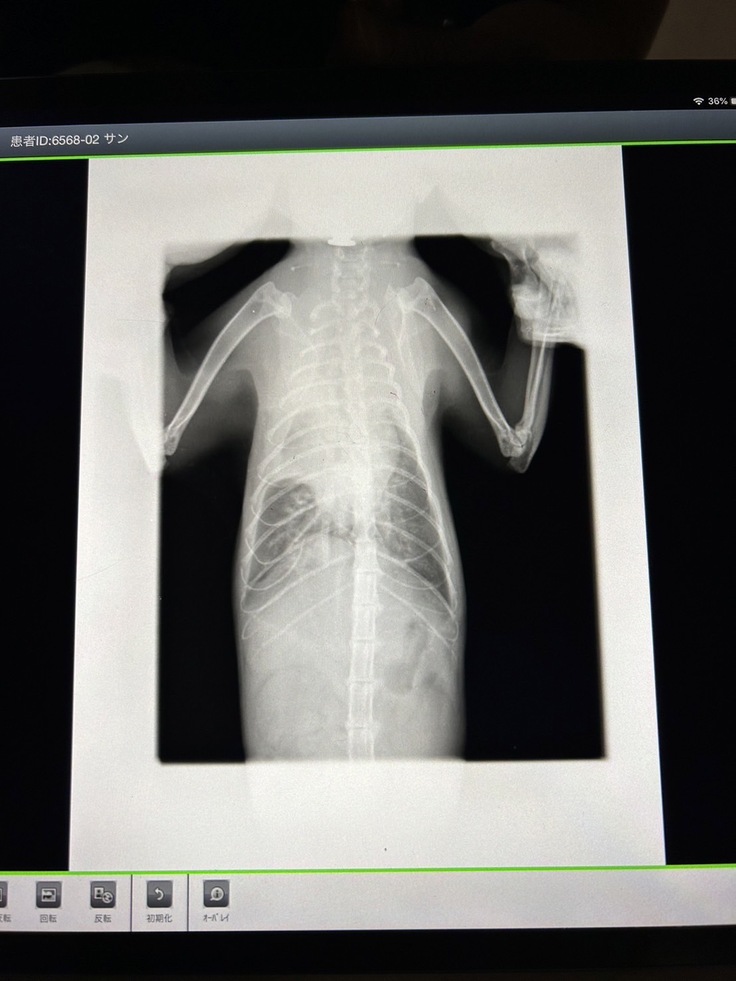

2/8 血液検査、レントゲン

2/22 血液検査、レントゲン、胸水60cc

3/7 血液検査、レントゲン、胸水90cc

3/14 血液検査、レントゲン、胸水140cc

3/21 血液検査、レントゲン、胸水160cc

3/28 レントゲン、胸水125cc

4/7 血液検査、レントゲン、胸水125cc

4/14 胸水197cc

胸部、水が溜まっている所が白濁しています

3月に入ると、水が溜まる頻度、量が増え始め、2週間毎の通院を1週間毎にした方が良いと獣医師から言われました。

また、点滴の量が肺に溜まる水量に大きく影響する為、利尿剤の薬と伴わせながら合間を取る治療がこの先も続きます。